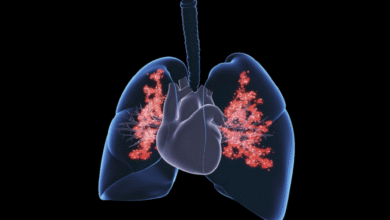

يعد مرض باركنسون اضطرابا تنكسيا متفاقما يؤثر بشكل مباشر على القدرة الحركية للجسم نتيجة موت الخلايا العصبية المنتجة لمادة الدوبامين، وهي ناقل عصبي ينتجه الدماغ ويلعب دورا مهما في عدة وظائف أساسية للجسم والعقل. ومع مرور الوقت، قد يصاب المرضى بتصلب شديد يفقدهم القدرة على الحركة والعناية الذاتية، بينما تركز العلاجات المتوفرة حاليا على تخفيف الأعراض دون معالجة السبب الجذري للمرض.